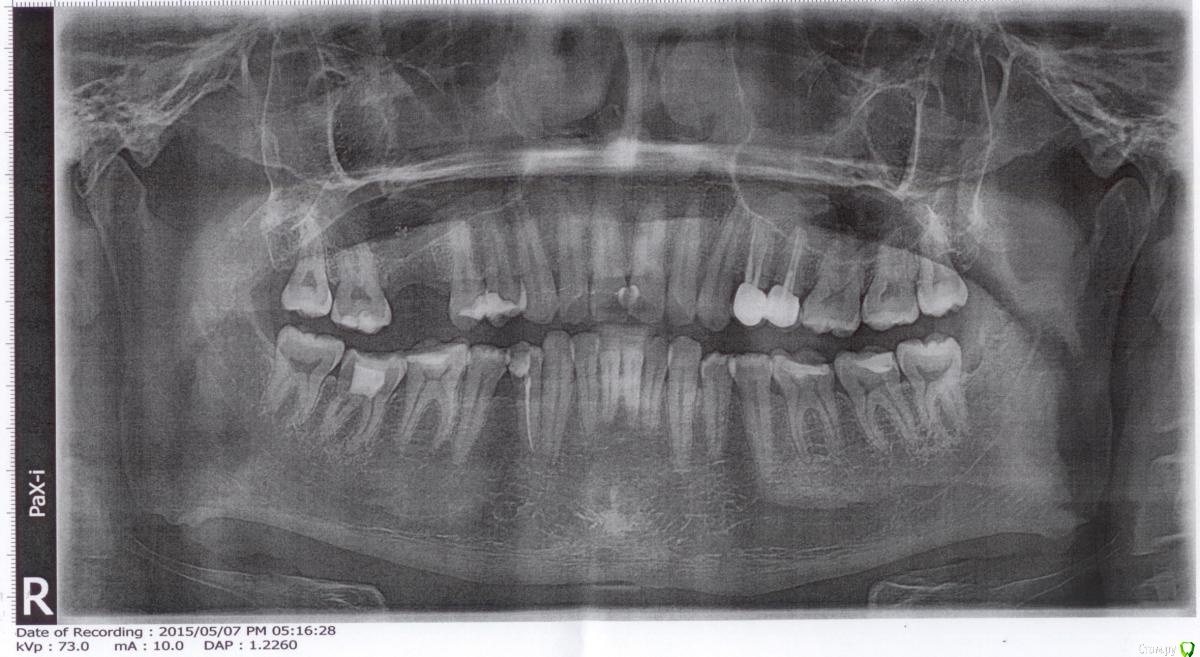

Kim_arz Опубликовано 11 мая, 2015 Поделиться Опубликовано 11 мая, 2015 Здравствуйте! Подскажите советом, необходима ли костная пластика и если да, то закрытая или открытая? 1 Ссылка на комментарий

diesel87 Опубликовано 11 мая, 2015 Поделиться Опубликовано 11 мая, 2015 Здравствуйте, если вы про синус в области 16 зуба, то необходим открыты синус лифт одномоментно с установкой имплантата. 2 Ссылка на комментарий